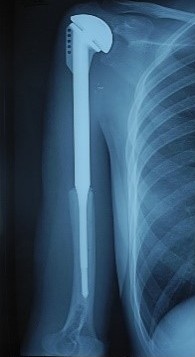

Рентгенограмма после эндопротезирования

Рентгенограмма после резекции и эндопротезирования просимльной ½ плечевой кости